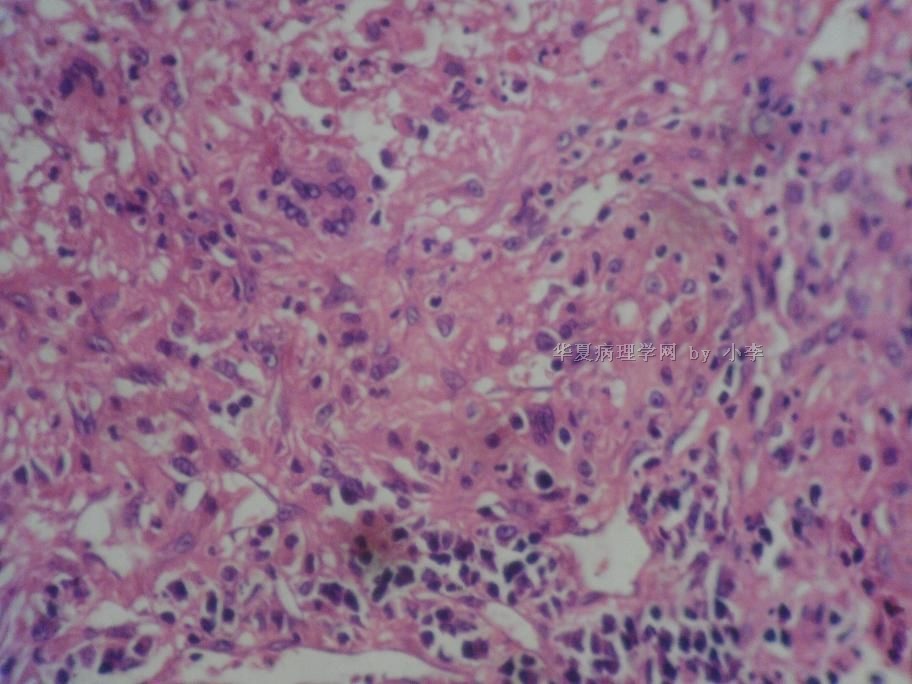

睾丸炎?

• 睾丸炎?图3

图3

首先考虑精子肉芽肿

肉芽肿性睾丸炎

精子肉芽肿